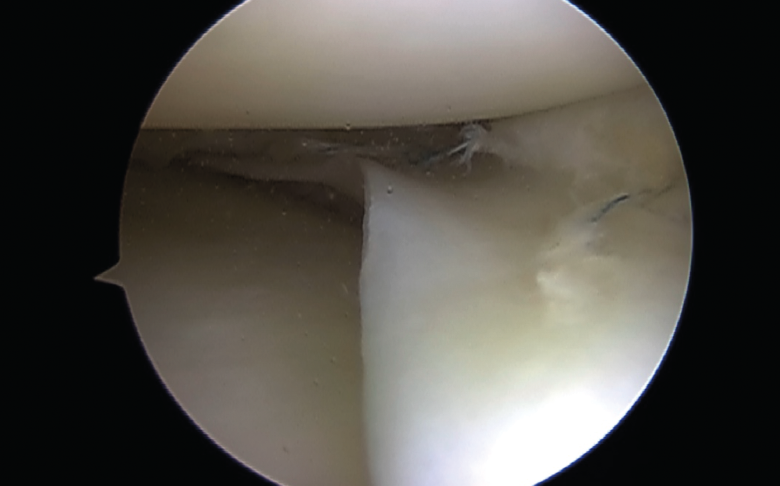

Biomecánicamente, se ha demostrado que una configuración de sutura vertical ya sea dentro-fuera o técnicas todo dentro cada 3 a 5 mm proporciona superioridad sobre la configuración horizontal(10)(Figura 4).

Figura 4. Asa de cubo: sutura con 3 puntos mediante técnica todo dentro.